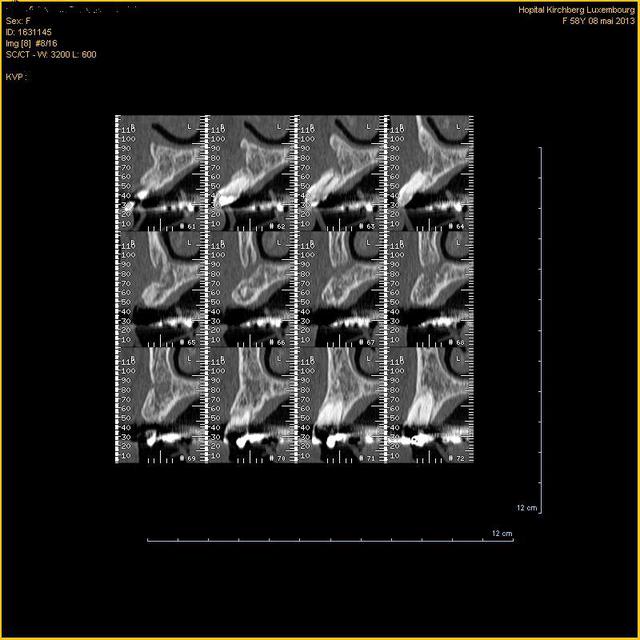

Patiente qui s'est fait extraire une 23 incluse et qui vient pour se faire placer un implant en 23

Sur le scanner(1 an après extraction), image 66-67, on voit une commnunication bucco-nasale.

Est-ce qu'on peut envisager traiter ça comme une communication bucco-sinusienne(membrane et rog) ou comment vous faites? Quel risque si on laisse cette communication et je propose un bridge 22-23-24 à la patiente à la place de l'implant.